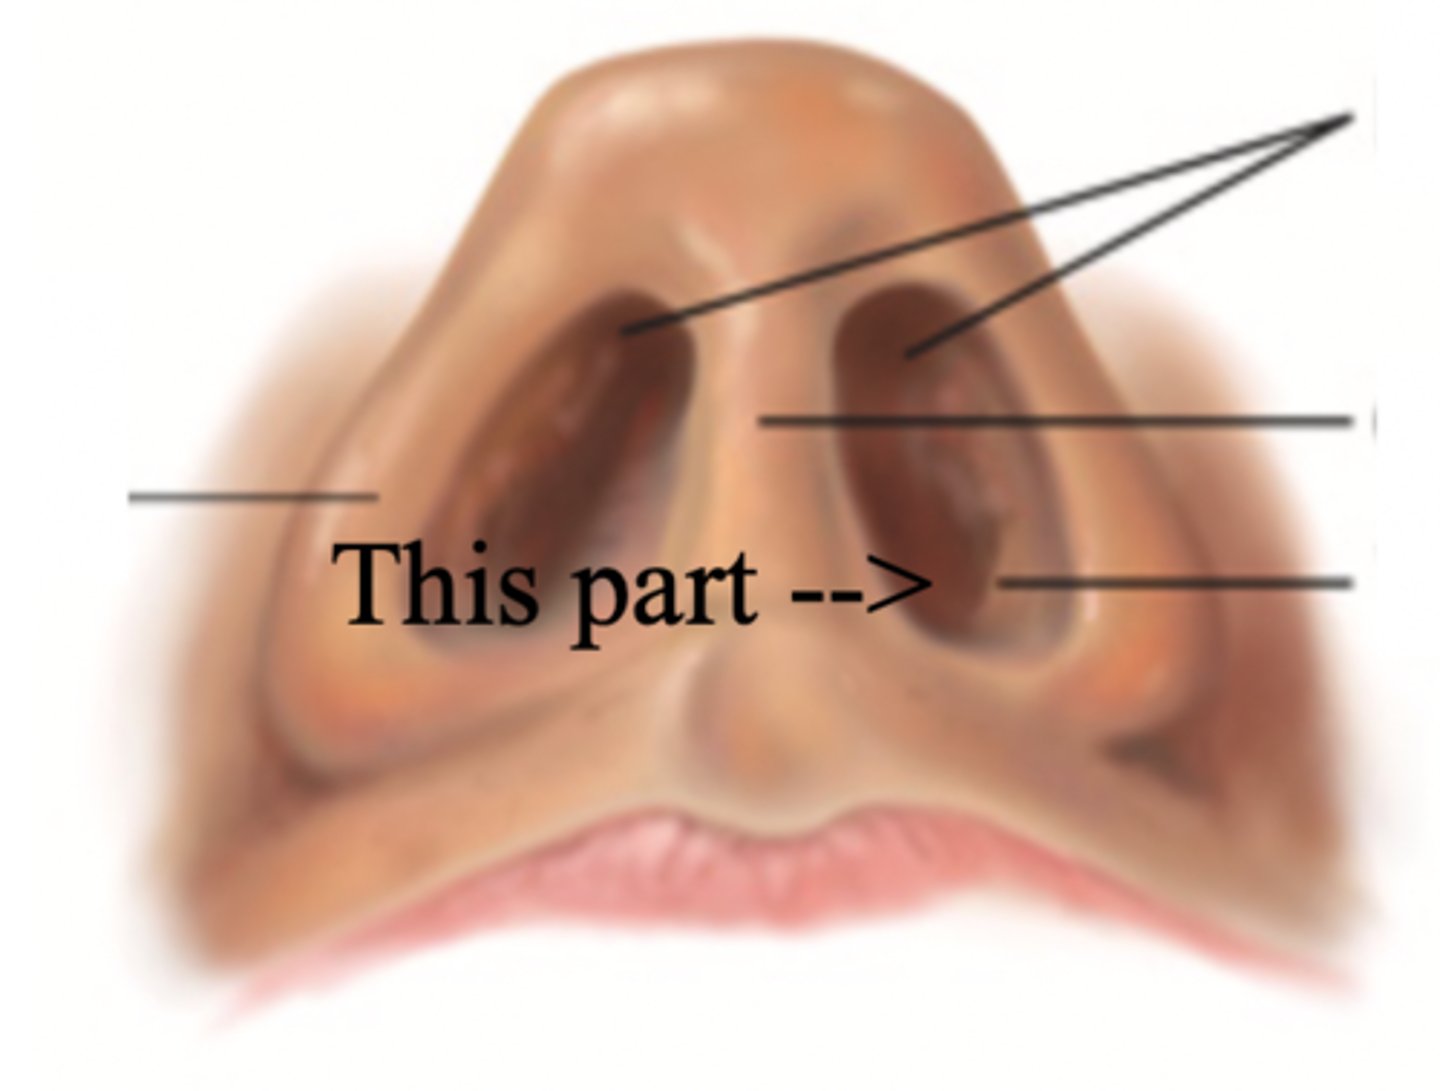

Nose

Organ of smell

Bridge

Tip

Ala

Nares

Columella

Vestibule